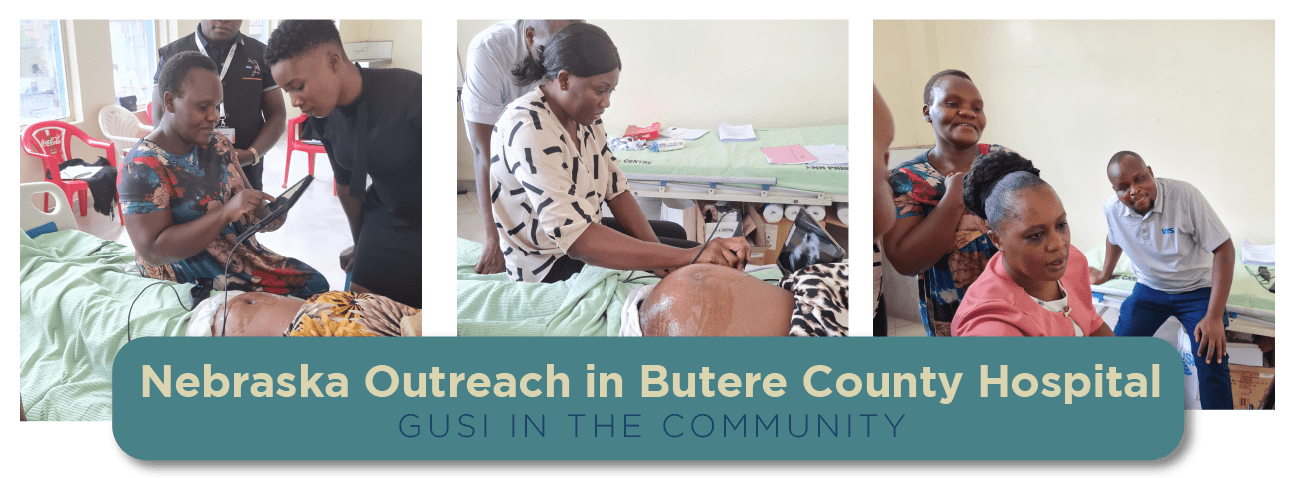

In a heartwarming display of community support, Nebraska Outreach came together to donate a crucial probe to Butere County Hospital in Kenya. Their generosity went beyond a crucial probe donation, extending to covering the entire cost of training. GUSI spearheaded Obstetrics (2nd and 3rd trimesters) training, a pivotal initiative that unfolded over five enlightening days, starting on January 8. The Nebraska community’s generosity and commitment have undoubtedly left a lasting impact on healthcare in Butere County, Kenya, fostering knowledge and empowerment.